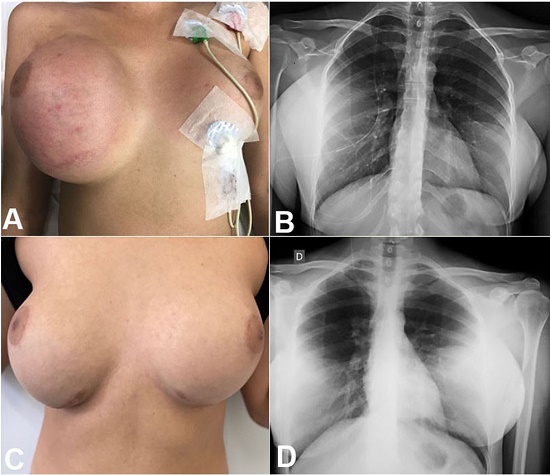

On clinical examination, the patient was awake and aware with no motor or cranial nerve impairments, the patient had bilateral papilledema in the fundus. The breast examination revealed an increase in the size of her right breast with inflammatory signs and a palpable liquid collection (Figure 1A).

The patient was submitted to ultrasonography, which showed the integrity of the silicone implant and the presence of the VPS catheter inside this capsule. An x-ray of the thorax and abdomen showed the distal catheter of VPS outside the abdomen and inside the right breast (Figure 1B).

Surgical revision of the VPS system was performed, revealing the distal catheter inside the right breast; however, outside the silicone implant, the catheter was placed medially and inside the peritoneal cavity.

Post-operatively, the size of the right breast decreased and became symmetrical with the left breast (Figure 1C). The patient’s headache and vomiting also improved.

At the 1-year follow-up, the patient was asymptomatic, the breast was still symmetrical, and the x-ray showed the satisfactory position of the distal catheter (Figure 1D).